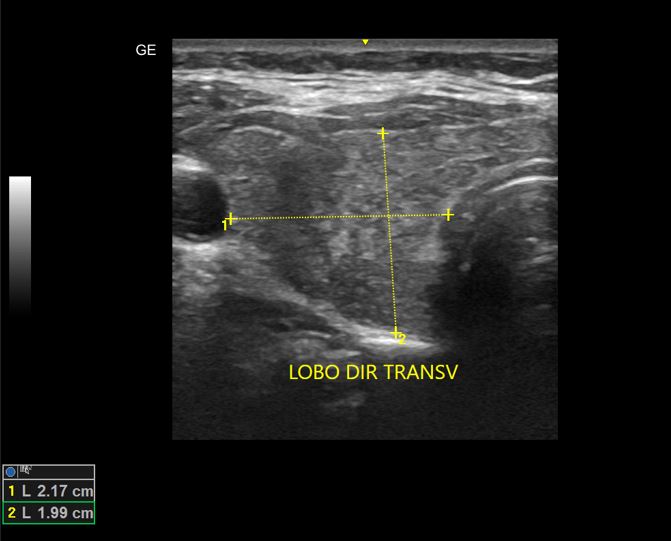

DOENÇA DE GRAVES COM BÓCIO

Associação de Graves com doença nodular.